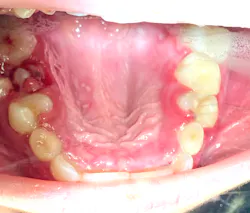

Diagnosis: Mesiodens tooth

For a recap on mesiodens teeth, diagnosis, and treatment, please refer to another case report I wrote that you might find of interest. Here is a quick- The lesions may occur “as single, multiple, unilateral, or bilateral (lesions); the presence of multiple supernumerary teeth is called ‘mesiodentes.’”1

- By way of appearance, they typically manifest in a conical- or peg-shaped form.2

- In general, supernumerary teeth—also referred to as hyperdontia or extra teeth—can occur in any location, but they are more prevalent in the maxilla (90%) as opposed to the mandible (10%).2

- The most common type of supernumerary teeth are mesiodentes.1 Their etiology remains unclear, although it is theorized that they are either an isolated finding or part of a “syndrome, specifically cleft lip and palate, cleidocranial dysostosis, and Gardner’s syndrome.”1

- Diagnosis is primarily via radiograph and can be confirmed by taking multiple angles using intraoral and extraoral radiographs (i.e., panoramic, periapicals, etc.). Furthermore, three-dimensional CBCT scans allow dialing in on the palatal location of the mesiodentes and their relationship to adjacent teeth. Delayed or altered eruptions of adult dentition also give rise to the suspicion of mesiodentes. Other common signs include cyst formation and crowding.

- Treatment of mesiodens varies. Although typically asymptomatic, they are “often extracted for aesthetic reasons, to allow the eruption of other teeth, orthodontic reasons, and/or suspected pathology.”3